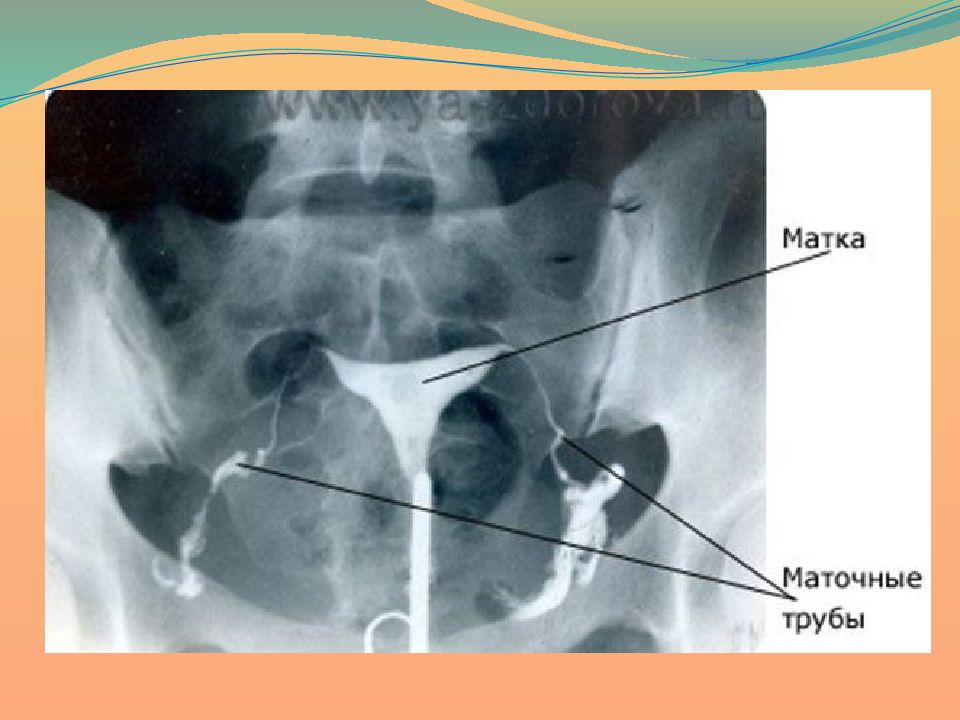

Медицинские снимки: Проходимость маточных труб

Раздел: Кадры-подсказки